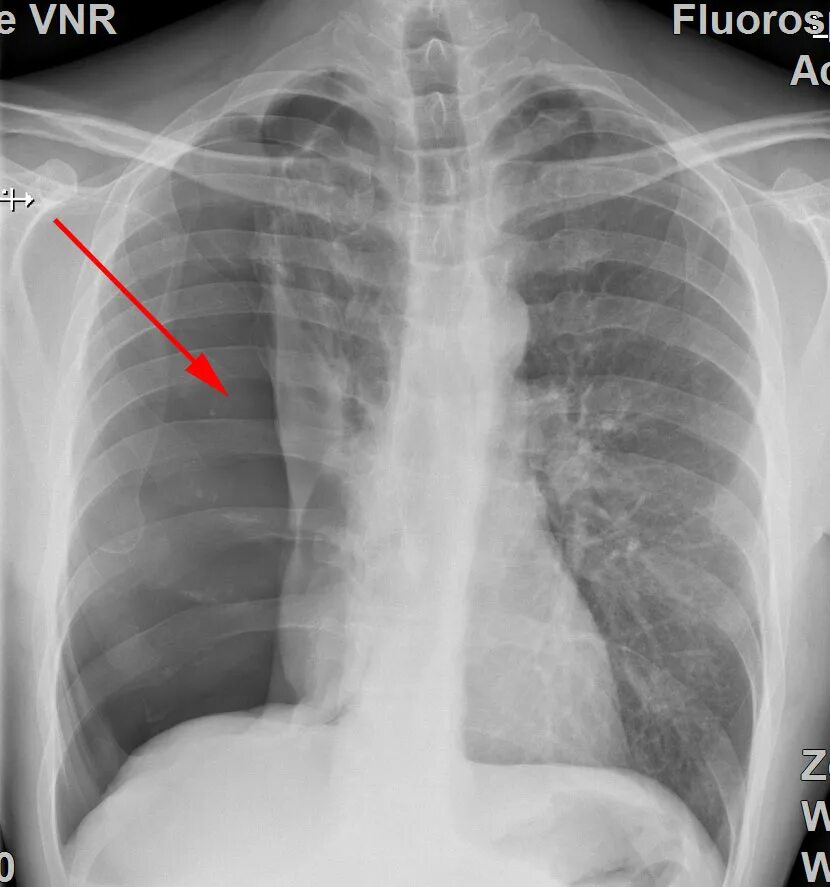

Коллапсотерапия при туберкулезе